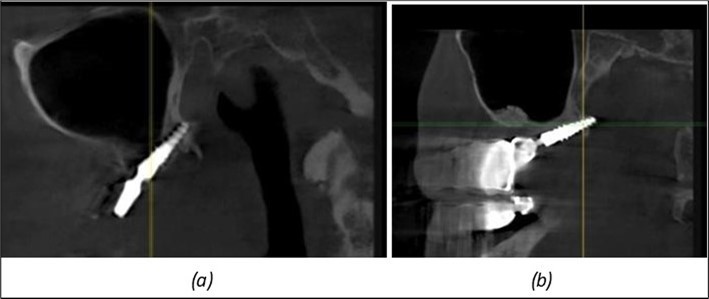

Figure 9.Implants in the pterygoid plateau area: (a) TPG implant fixed in the maxillary-sphenoid junction area, quadrant 1; (b) TPG implant fixed in the maxillary-sphenoid junction area, quadrant 2.

Figure 10.Implants in the palatal sinus cortical area to avoid bone grafting: (a) BCS implant partially fixed in the graft material mass, partially in the palatal cortex; (b) Implant fixed in the palatal cortex at the junction with the nasal cortex, behind the graft material mass.

Figure 11.Implants in the anterior area anchored in the nasal cortex (BCS and TPG): (a), (c) – BCS implants fixed in the nasal cortex; (b), (d) – TPG implants fixed in the second nasal cortex with compression in the trabecular area.

Figure 12.Implants fixed distally in quadrant 4 with fixation at the level of the mylohyoid line: (a) The most distal implant fixed in unaffected bone from the previous restoration; (b) The implant fixed in the area where the two stage implant was removed.